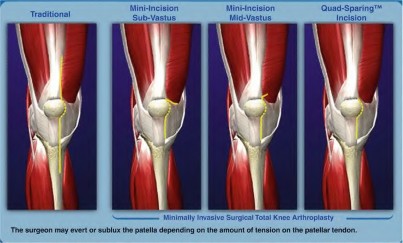

A patient who has previously undergone a high tibial osteotomy 10 years prior is scheduled for a total knee arthroplasty (TKA). Which of the following factors is most likely to be present and may complicate the arthroplasty?

TKA after a high tibial osteotomy (HTO) can be more difficult to perform than a primary knee replacement because of a shift of the proximal tibial articular surface in relation to the medullary canal, retained hardware, previous skin incisions, scar tissue, and altered patellofemoral mechanics caused by patella baja and contraction of the patella tendon. The frequency of valgus deformity is greater following HTO.